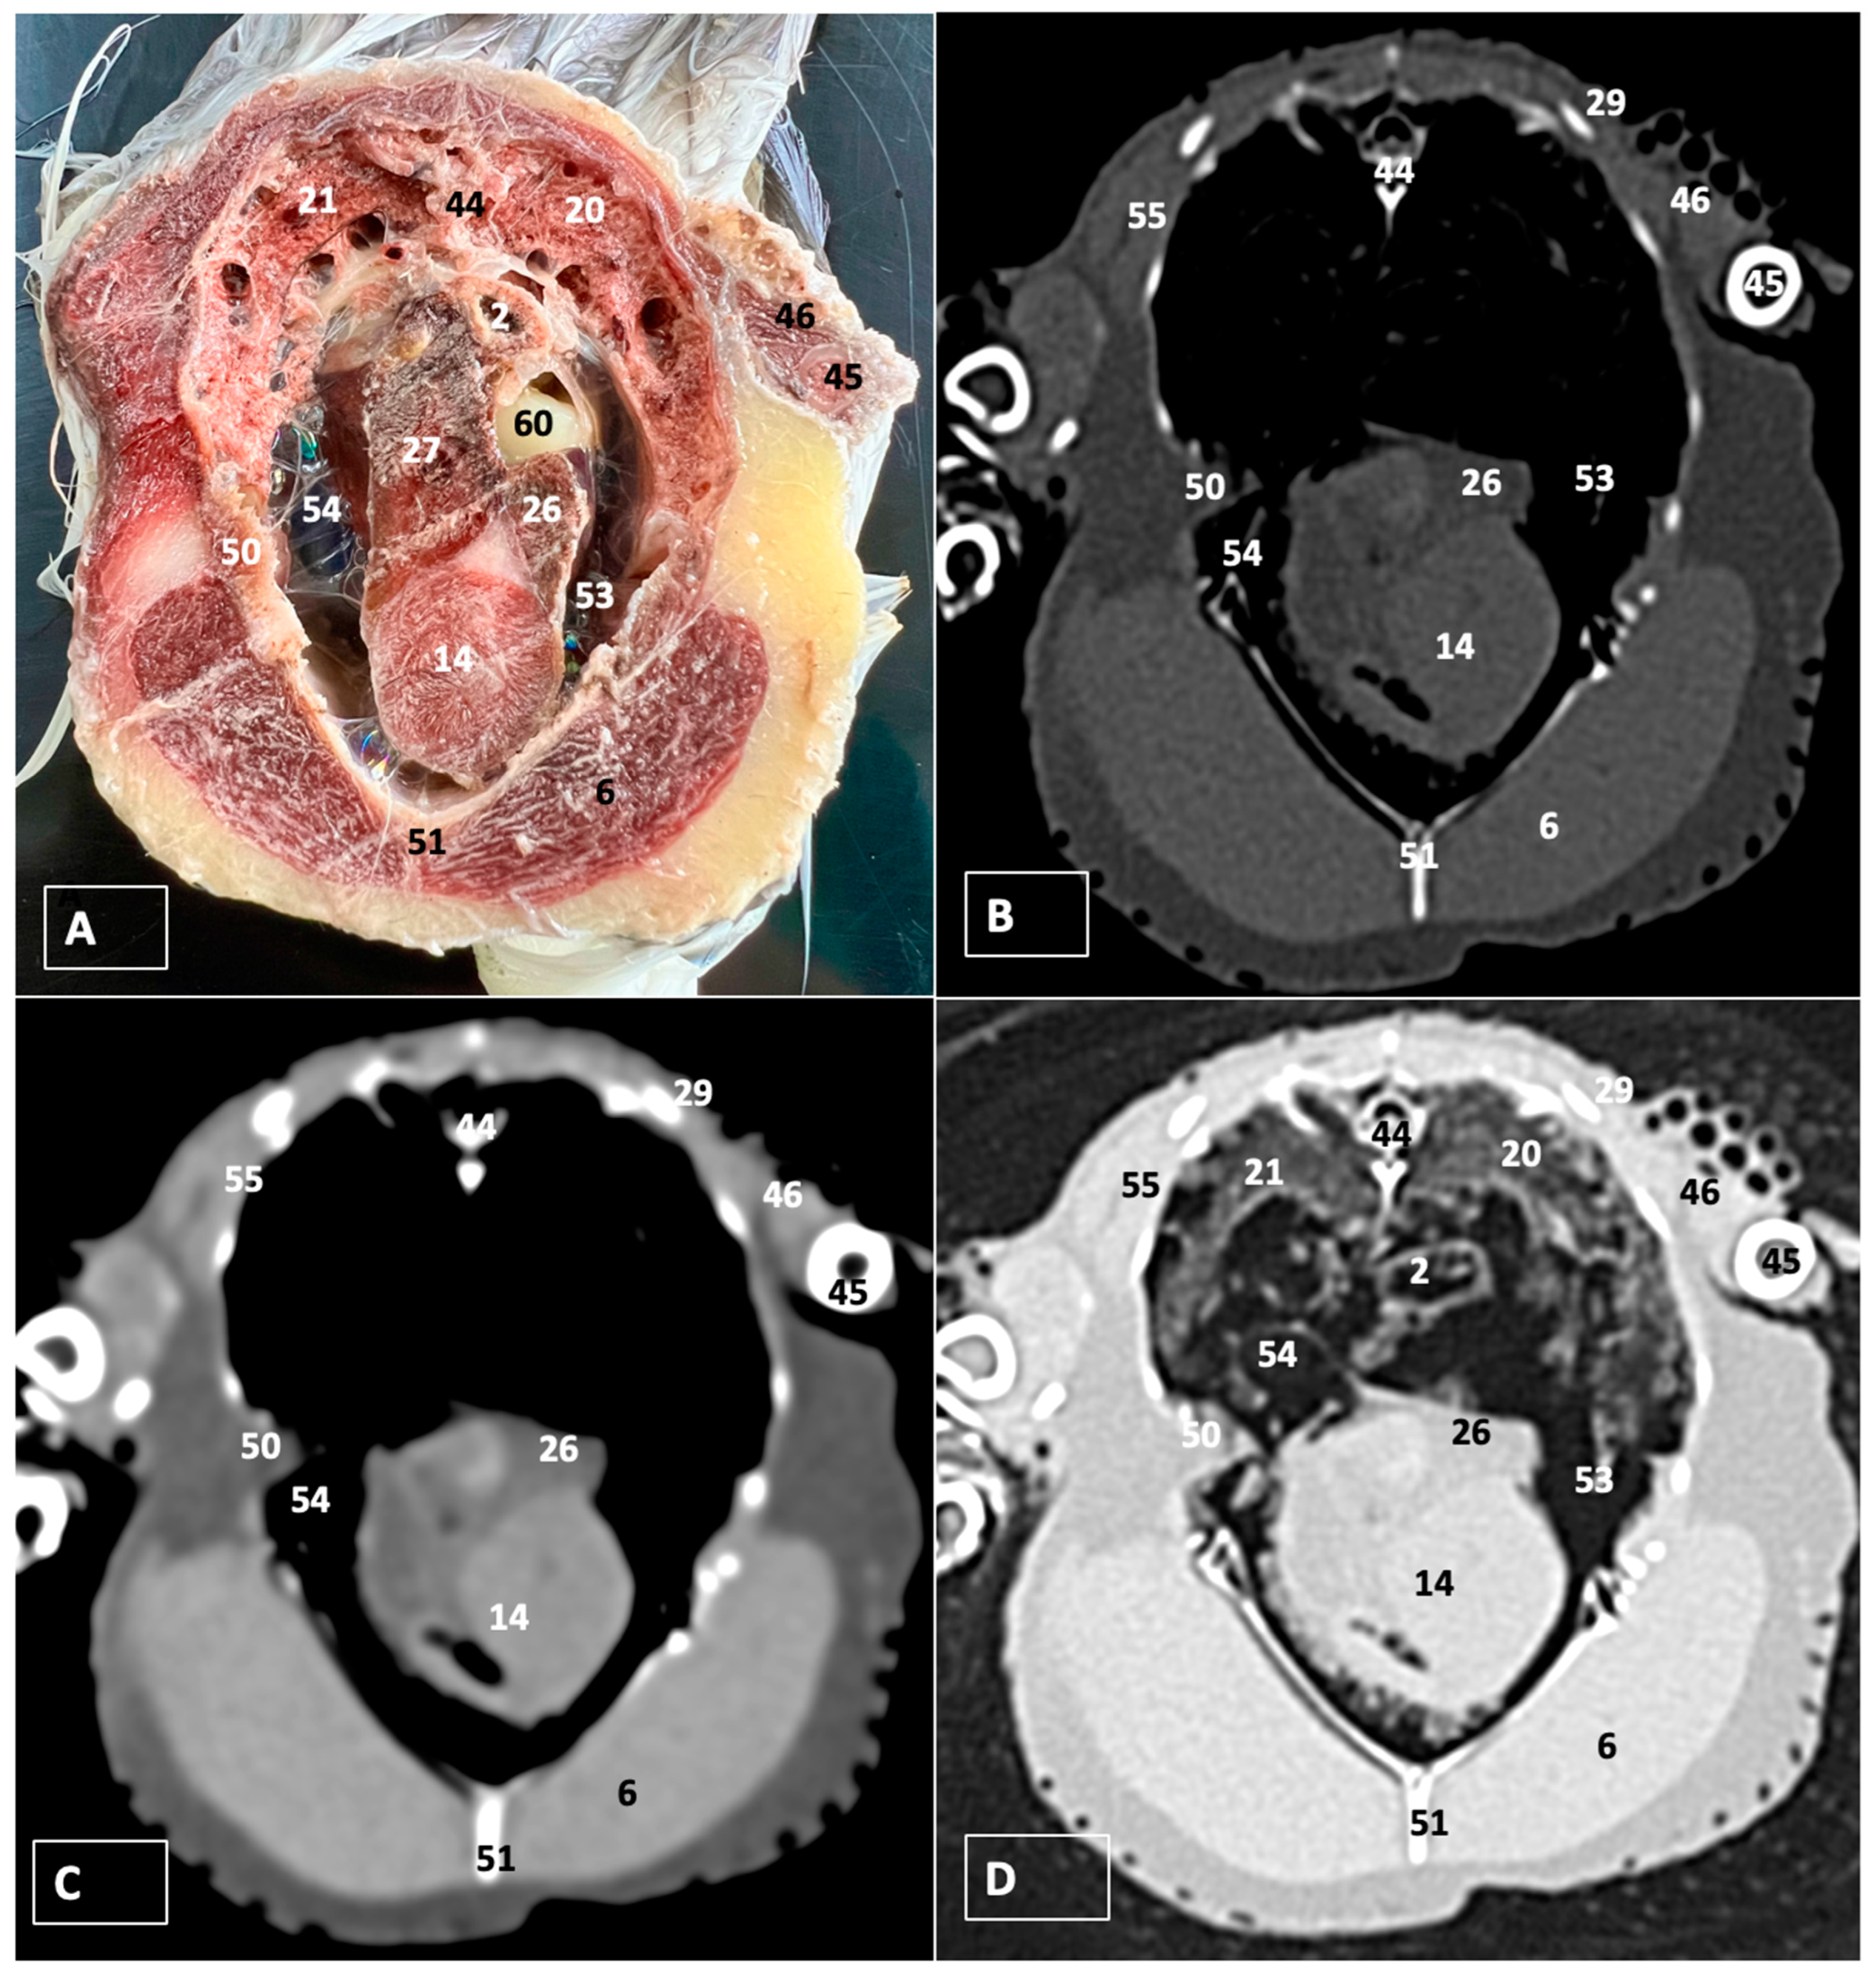

3.1. Anatomical Dissections and Cross-Sections

3.2. Computed Tomography Images